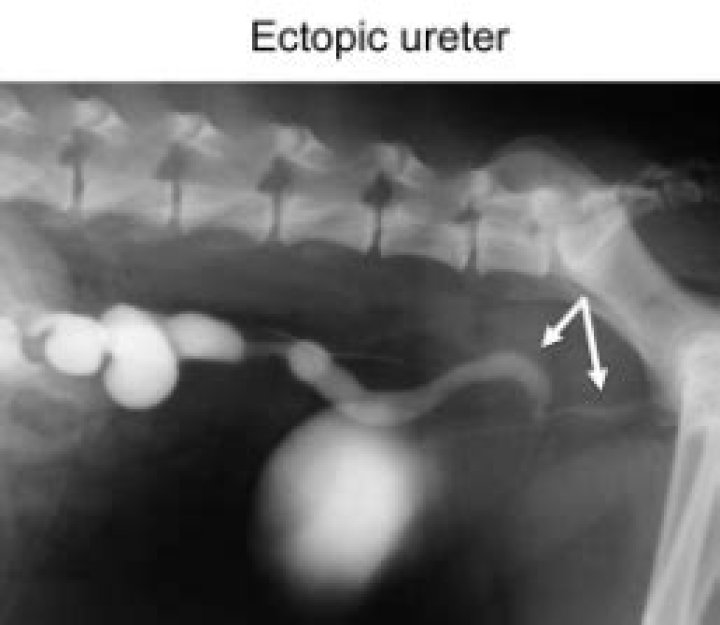

An intravenous pyelogram (PIE-uh-low-gram), also called an excretory urogram, is an X-ray exam of your urinary tract. An intravenous pyelogram lets your doctor view your kidneys, your bladder and the tubes that carry urine from your kidneys to your bladder (ureters).

Excretory urography, also known as intravenous pyelogram, is performed using conventional x-ray after the intravenous administration of radiographic contrast material.